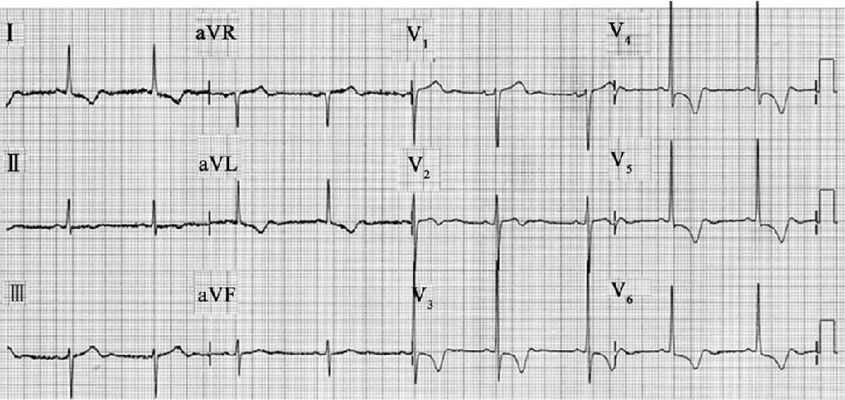

預激綜合徵心電圖 (9)

預激綜合徵心電圖 (90)

預激綜合徵心電圖 (91)

預激綜合徵心電圖 (92)

預激綜合徵心電圖 (93)

預激綜合徵心電圖 (94)

預激綜合徵心電圖 (95)

預激綜合徵心電圖 (96)

A:預激綜合徵典型的心電圖表現是竇性心搏的PR間期縮短,短於0.12s,而且導聯的QRS波群時間超過0.12s。QRS波群起始部分會有粗鈍,終末部分正常,甚至會導致ST-T波型呈現繼發性的改變,甚至於QRS波群主波方向相反。預激綜合徵是指心房……

A:預激綜合徵是很少見的心律失常,是房室傳導異常的一種類型,提早興奮心室的一部分或全部,引起心室肌提前激動,常合併室上性心動過速。心電圖可見PR間期縮短小於0.12秒;QRS時限延長0.11秒以上;QRS波群起始部粗鈍,繼發性ST-T改變。沒有……

A:預激綜合徵合併房速的時候,心電圖可以出現快速而且寬大畸形的QRS波群,有點類似於室性心動過速,典型的預激波有可能會被覆蓋。合併房速的時候會有極快速的心室率、QRS波群會寬大畸形,也有可能比較易變和複雜。患有預激綜合症合併房速,如果有明顯的心……